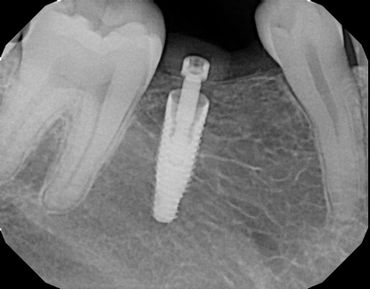

The Neodent GM Guided Surgery Kit is a compact, easy to use guided surgery system. Clinicians can provide CT scan, digital photos, and impressions to a laboratory for precise implant guide fabrication. Temporary teeth can be made and the lab will know the depth, angle, and timing of the connection of the implant. This allows you better esthetics and provides the patient teeth the same day with less chair time.

The Dental Future Center, Dr Bernee Dunson, and 3DDX Implant Guided Surgery course.